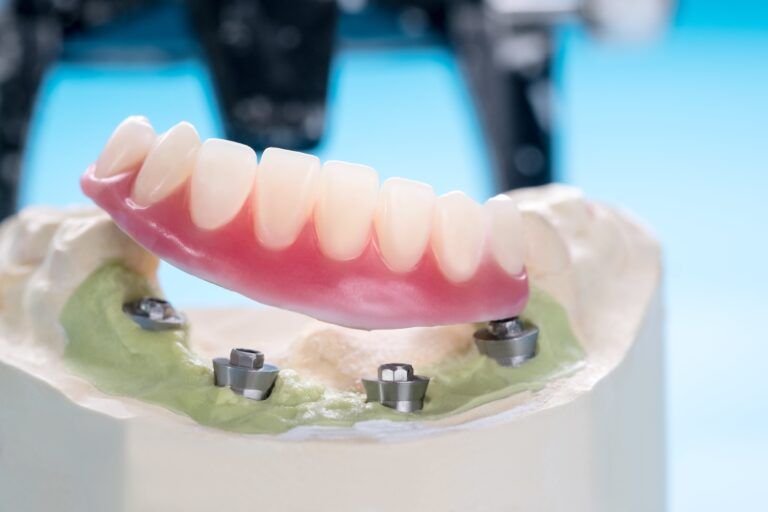

Complete Implant-Supported Dentures: An Overview

When it comes to restoring a natural smile and enhancing oral functionality, dentures have long been a reliable solution. However, traditional dentures can sometimes pose challenges such as instability and discomfort. Enter implant-supported dentures—a modern and innovative approach that offers

Implant-Supported Dentures: Combining the Best of Both Worlds

When it comes to replacing missing teeth, dentures have long been a popular choice. However, traditional dentures come with their fair share of challenges and discomforts, from slipping and sliding to difficulty eating certain foods. Fortunately, modern dentistry has brought